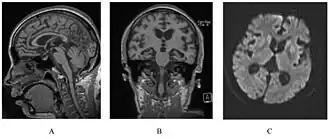

Het syndroom van Gerstmann-Sträussler-Scheinker, meestal afgekort tot GSS, is een zeer zeldzame, altijd dodelijk verlopende hersenziekte die door prionen wordt veroorzaakt. Patiënten gaan trillen, krijgen ataxie en dementeringsverschijnselen en overlijden binnen enkele jaren na het ontstaan van de eerste symptomen.

Bijzonder is dat die prionen in dit geval spontaan ontstaan door een abnormaal eiwit dat een andere configuratie heeft dan bij gezonde mensen. Omdat de structuur van dit eiwit erfelijk is bepaald, komt deze ziekte in bepaalde families volgens een duidelijk erfelijk autosomaal dominant patroon met nagenoeg volledige penetrantie voor. De ziekte is daarnaast overdraagbaar op mensen en chimpansees.